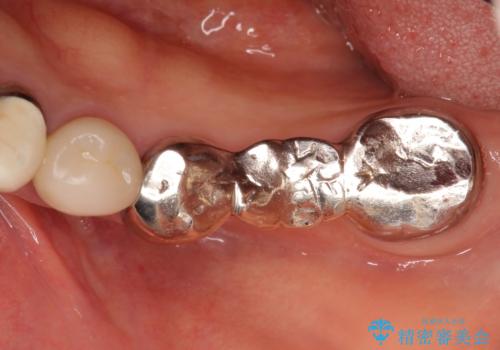

- 毎回食事のたびに食べかすがつまり、見た目も気になる銀歯のブリッジやりかえを希望され来院されました。

- 35万円(仮歯・ファイバーコア・ジルコニアクラウン×3)費用は治療当時の料金となります